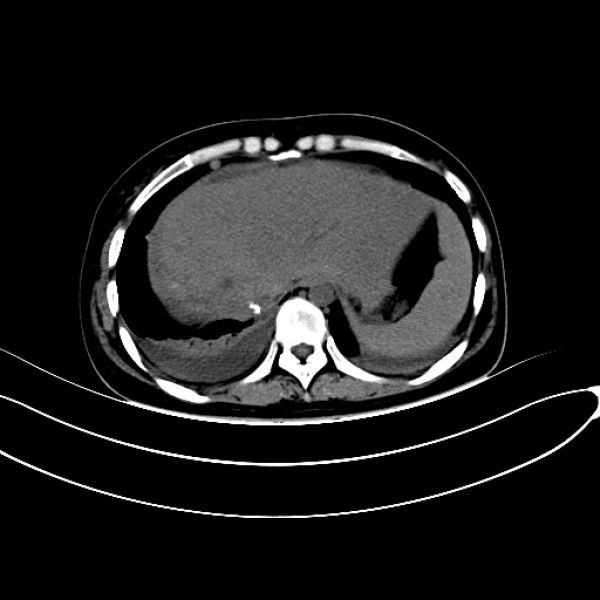

患者转入ICU治疗3天病情稳定后转湘雅医院继续治疗,并再次行肝创面压迫止血棉垫取出术,经积极治疗,患者恢复良好。治疗过程中两次行彩超引导下肝脓肿穿刺引流术,术后病情平稳,恢复出院。患者出院后,因肝脓肿反复住院数次进行脓肿冲洗引流,给患者生理和心理带来了很大影响。8月10患者以“肝脓肿穿刺引流术后3月余”来肝胆一科住院复查治疗,完善肝胆脾CT检查后发现,患者右肝脓肿仍然明显。王文儿主任组织肝胆一科医师进行科内讨论研究指出,通过仔细研究CT片及结合分析患者抢救治疗经过后认为要根治性解决患者目前病灶,必须行右半肝切除。经过与患者家属沟通,仔细说明患者目前病灶情况及治疗方案的利弊之后,家属充分了解并同意手术方案。经过充分术前准备后,于8月14日在全面插管下行右半肝切除+右隔下脓肿清除引流术,术后经积极治疗,患者顺利康复出院。

术前CT图像